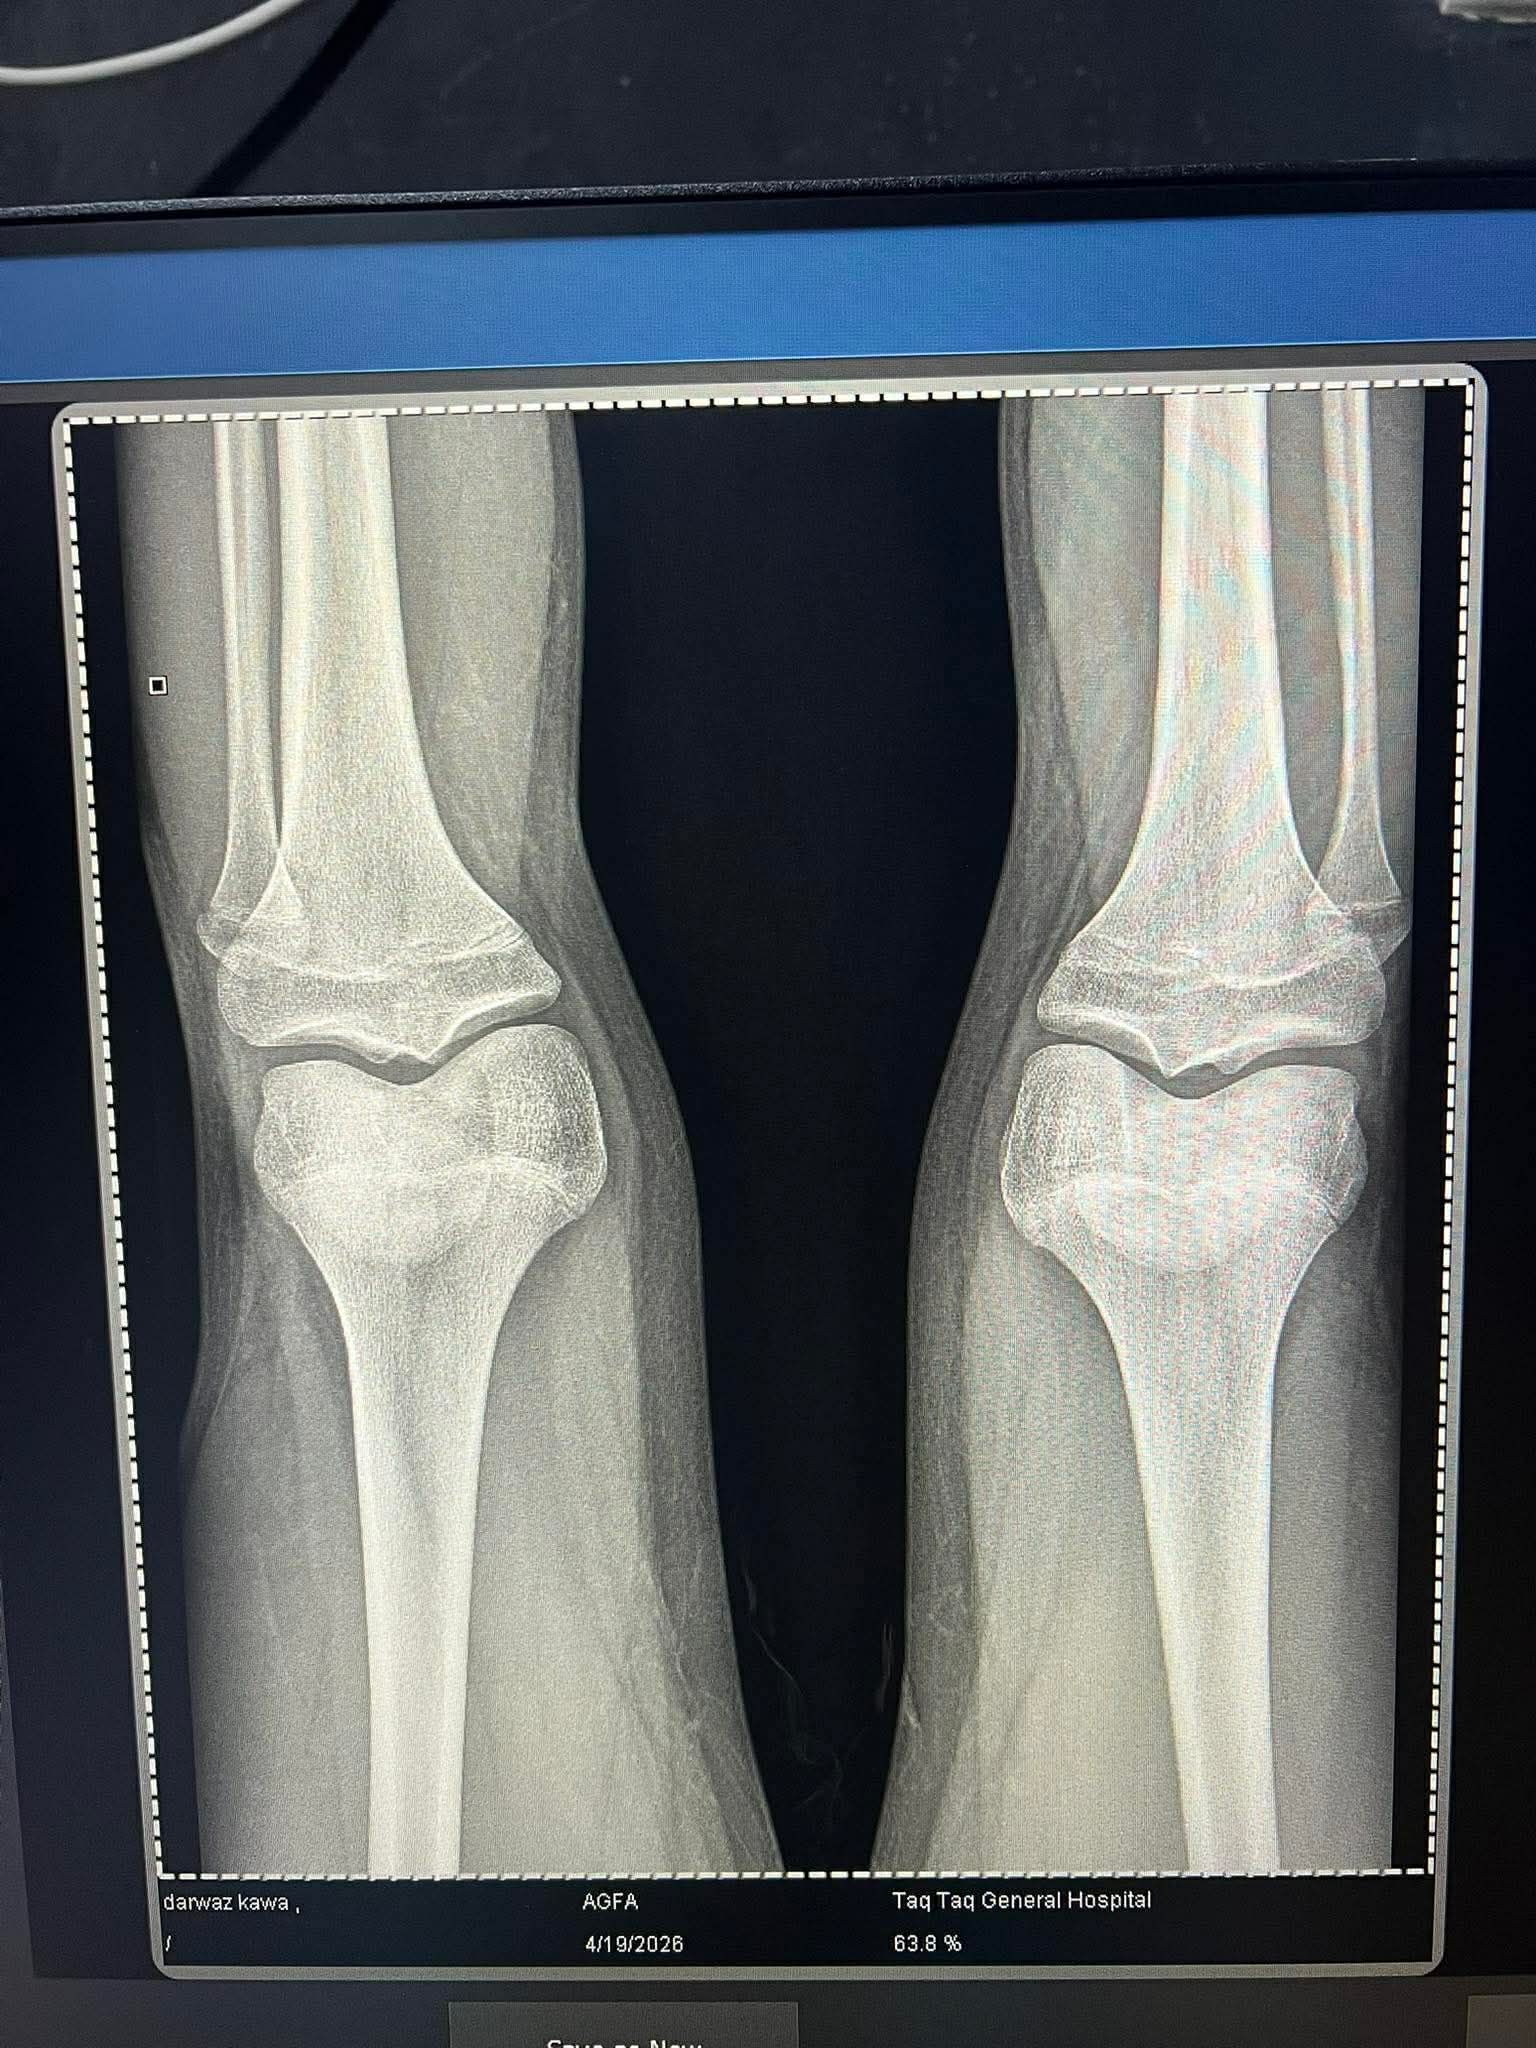

The doctor told me theres still space leftshits closed

yeah like deadass 0.1 of a cmThe doctor told me theres still space left![]()

Is there no hope if i use aiyeah like deadass 0.1 of a cm